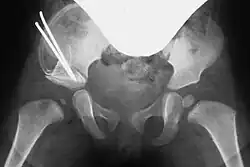

Entsprechend dem so entstandenen Spalt wird bei beiden Vorgehensweisen ein passender Knochenkeil (Spenderknochen/Knochenbank, siehe unten) zurechtgesägt und unter Röntgenkontrolle in den Spalt eingestößelt. Der Keil kann wenn nötig mit einem Osteosynthese-Draht (auch Kirschner-Draht genannt) fixiert werden. Bei einem geübten Operateur dauert diese Operation in etwa fünfundvierzig bis sechzig Minuten.[1][8]

Im Anschluss an die Operation wird ein entsprechender Beckenbeingips (modifizierter Fettweiss-Gips) oder eine Abduktions-Orthese angelegt, damit der Hüftkopf während der postoperativen Heilung zentral in der Pfanne steht. Die Narkose wird erst im Anschluss daran beendet.[4]